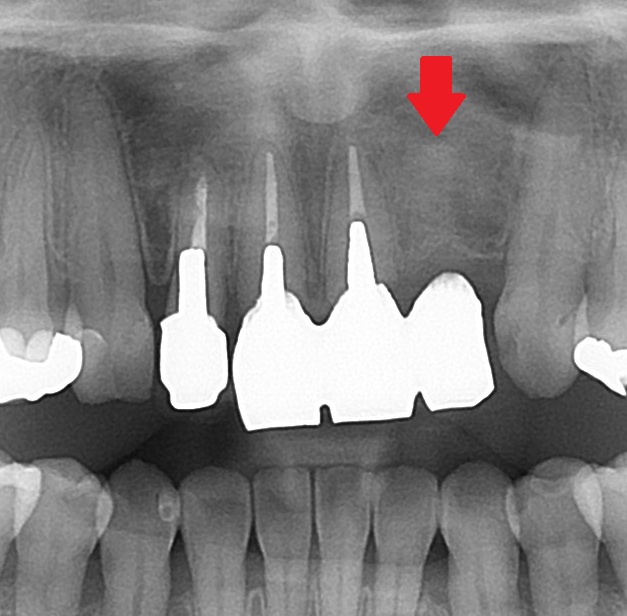

エックス線を見てみると

こちらの矢印の歯のコアが、太く、適正な方向に入っていないためです。方向がそれています。

斜めに埋め込まれてしまっており、赤い矢印の部分の歯の残量が無いためです。既に穴が開いているかもしれません。

このコアを外す際に、赤い矢印の箇所に穴が開くか、割れる可能性があります。

現在、歯に症状が無いために、このまま現状を維持することを患者さんと相談しました。